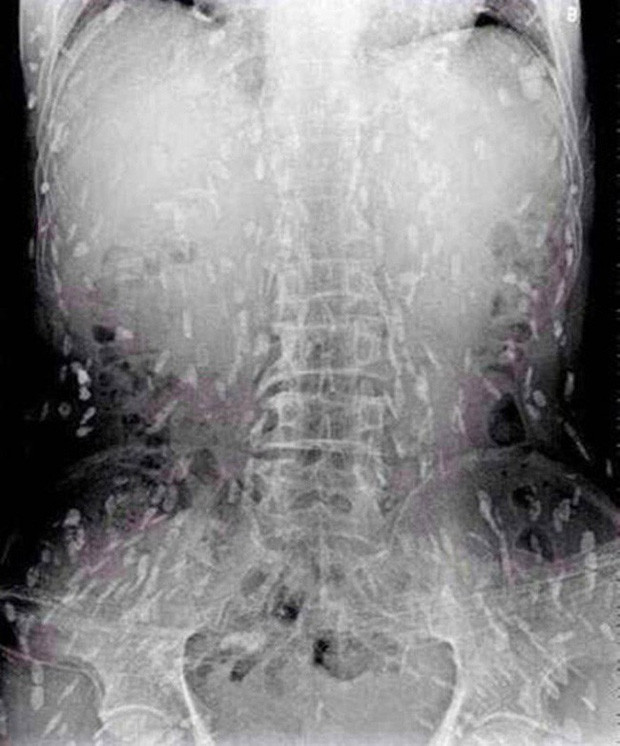

Sau khi chụp X-quang để kiểm tra, bác sĩ phát hiện gan của bệnh nhân lúc nhúc sán, được chẩn đoán mắc sán lá gan. Sán lá gan thường gặp ở các bệnh nhân ăn cá nước ngọt chưa nấu chín.

| Hình ảnh sán lúc nhúc dày đặc trong gan bệnh nhân. |

Tuy nhiên, do bệnh tình đã bước sang giai đoạn nghiêm trọng nên người đàn ông tiếp tục được chuyển tới Bệnh viện Nhân dân số 8 ở Quảng Châu để điều trị. Kết quả chụp X-quang cho thấy, những đốm trắng nhỏ xuất hiện lấm chấm khắp cơ thể chính là sán.